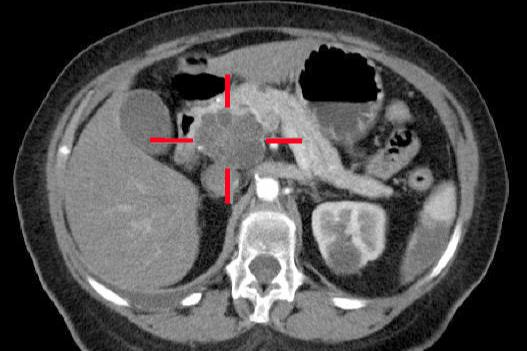

ஆதாரம்: ஜெர்மன் விக்கிபீடியாவில் MBQ

சி.டி ஸ்கேனர் பிரிவு, ஒரு மாறுபட்ட ஊடகத்தின் நரம்பு ஊசி போட்ட பிறகு, கணையத்தின் தலைப்பகுதியில் ஒரு அடினோகார்சினோமா புற்றுநோய் கட்டியைக் காட்டுகிறது.